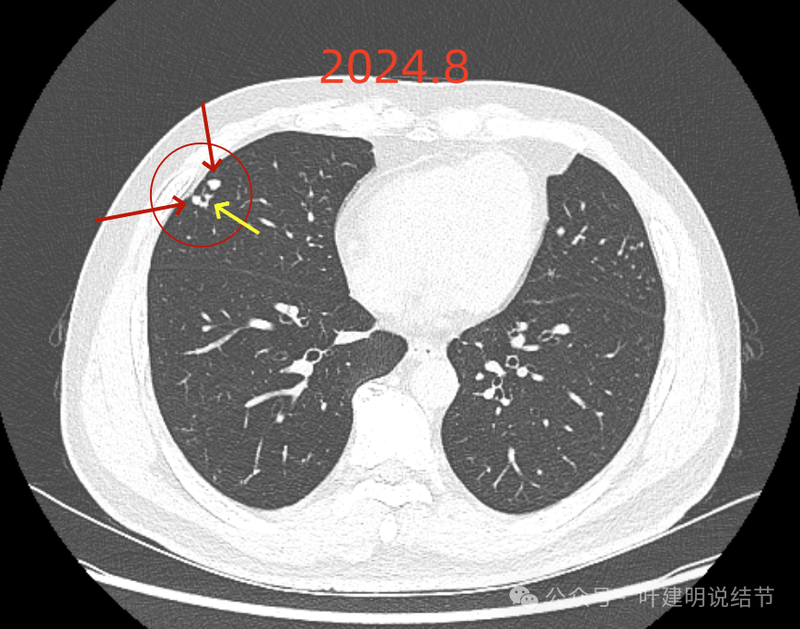

右上叶实性结节,边缘不光滑,有血管征,内部密度稍不均,整体轮廓较为清楚。

主病灶冠状位见血管紧挨,膨胀性不够。

血管征明显。

边缘区显得毛糙。